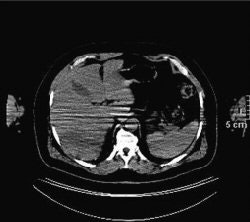

| The diagnostic CT image (top) shows a patient with colorectal cancer with hepatic metastasis in the left hepatic lobe (arrow), but it is not on PET/CT (above). The corresponding PET image (below) confirms metastasis. The study notes that treatment was not changed, as it was seen by PET scan. "Limitations of CT during PET/CT" (Journal of Nuclear Medicine, Vol. 48:10, pp. 1583-1591). Reprinted by permission of SNM. |

The discrepancy due to the lack of intravenous contrast material "most often led to undetected liver metastases or poor lymph node recognition, and most often was apparent in patients who were likely to have liver metastases and undergo PET/CT -- that is, patients with colorectal cancer," the researchers wrote.

In addition, they noted that some metastases could be seen on PET/CT "if a wide window/level was applied to the CT image or if the metastases were large or metabolically active enough to be seen on PET."